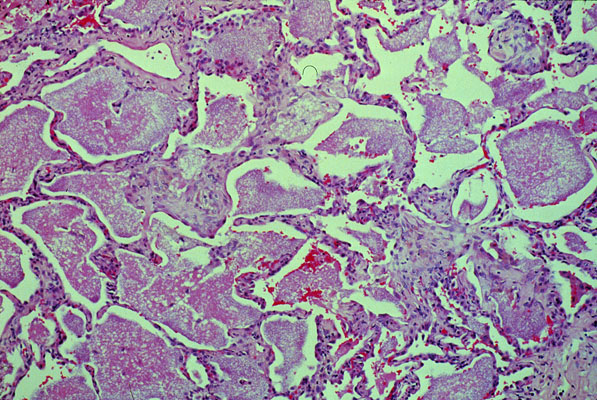

Pneumocystis carinii pneumonia

There is evidence of an interstitial pneumonitis; however, the most characteristic and prominent feature is the intra-alveolar frothy exudate. Alveolar spaces are filled with pink bubbly relatively acellular material forming cast-like structures.